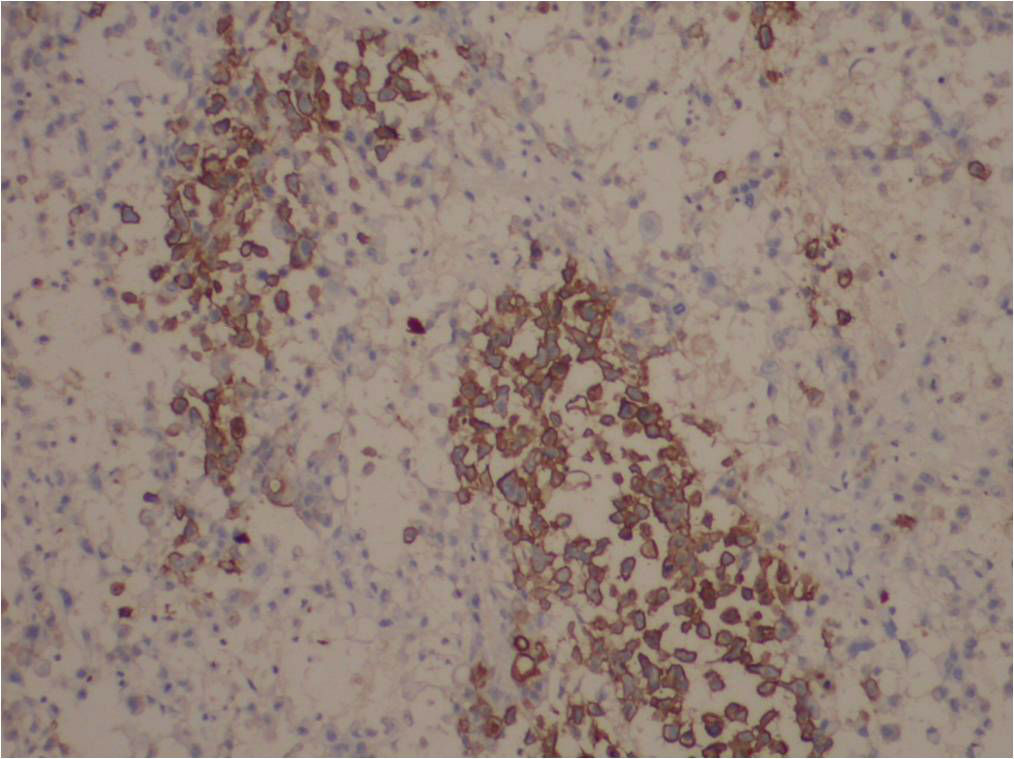

• 图1

• 图2

• 图3

• 图4

• 图5

免疫组化结果:

阳性: CKVimCD34EMA均(+),P63(灶+),CEA个别细胞(+), Ki6770%+)。

阴性: CD31MyogeninMyoD1desminactinCD68LysCK5/6均(-)。

特染: PAS-)。

最后诊断:

(外阴)近端型上皮样肉瘤。 (proximal-type epitheliod sarcoma, PES)